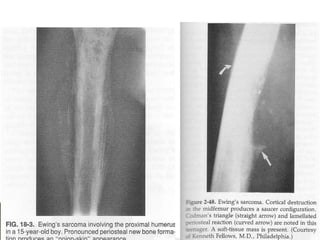

   X-RAY

◦ Moth eaten lesion

◦ Lytic or mixed lytic-sclerotic areas

present

◦ Multi-Layered subperiosteal reaction

(onion skinning)

◦ Lifting of perioteum (codman’s

triangle)